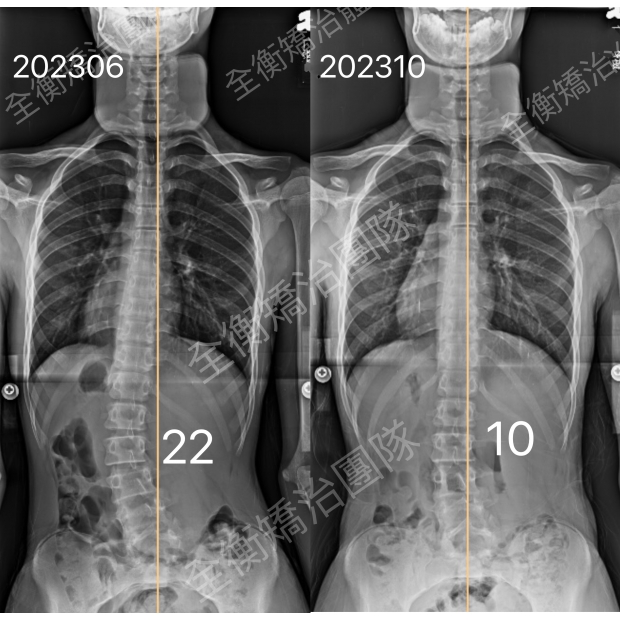

17歲中度側彎男生,積極矯治4個月,度數降低一半17歲中度側彎男生,積極矯治4個月,度數降低一半

17歲,骨齡3,腰彎22度男生,經過4個積極矯治:穿背架+復健運動

度數從22度改善至10度,減少了55% -